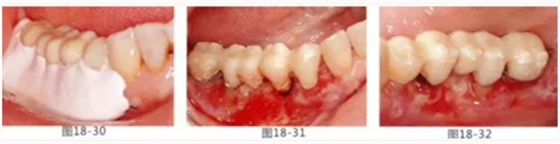

圖18-30 在頰側(cè)以及舌側(cè)涂上牙周塞治劑。然后將咬合面少許削除。

圖18-31 手術(shù)完成1周的頰側(cè)面照。

圖18-32 同部位的舌側(cè)面照。